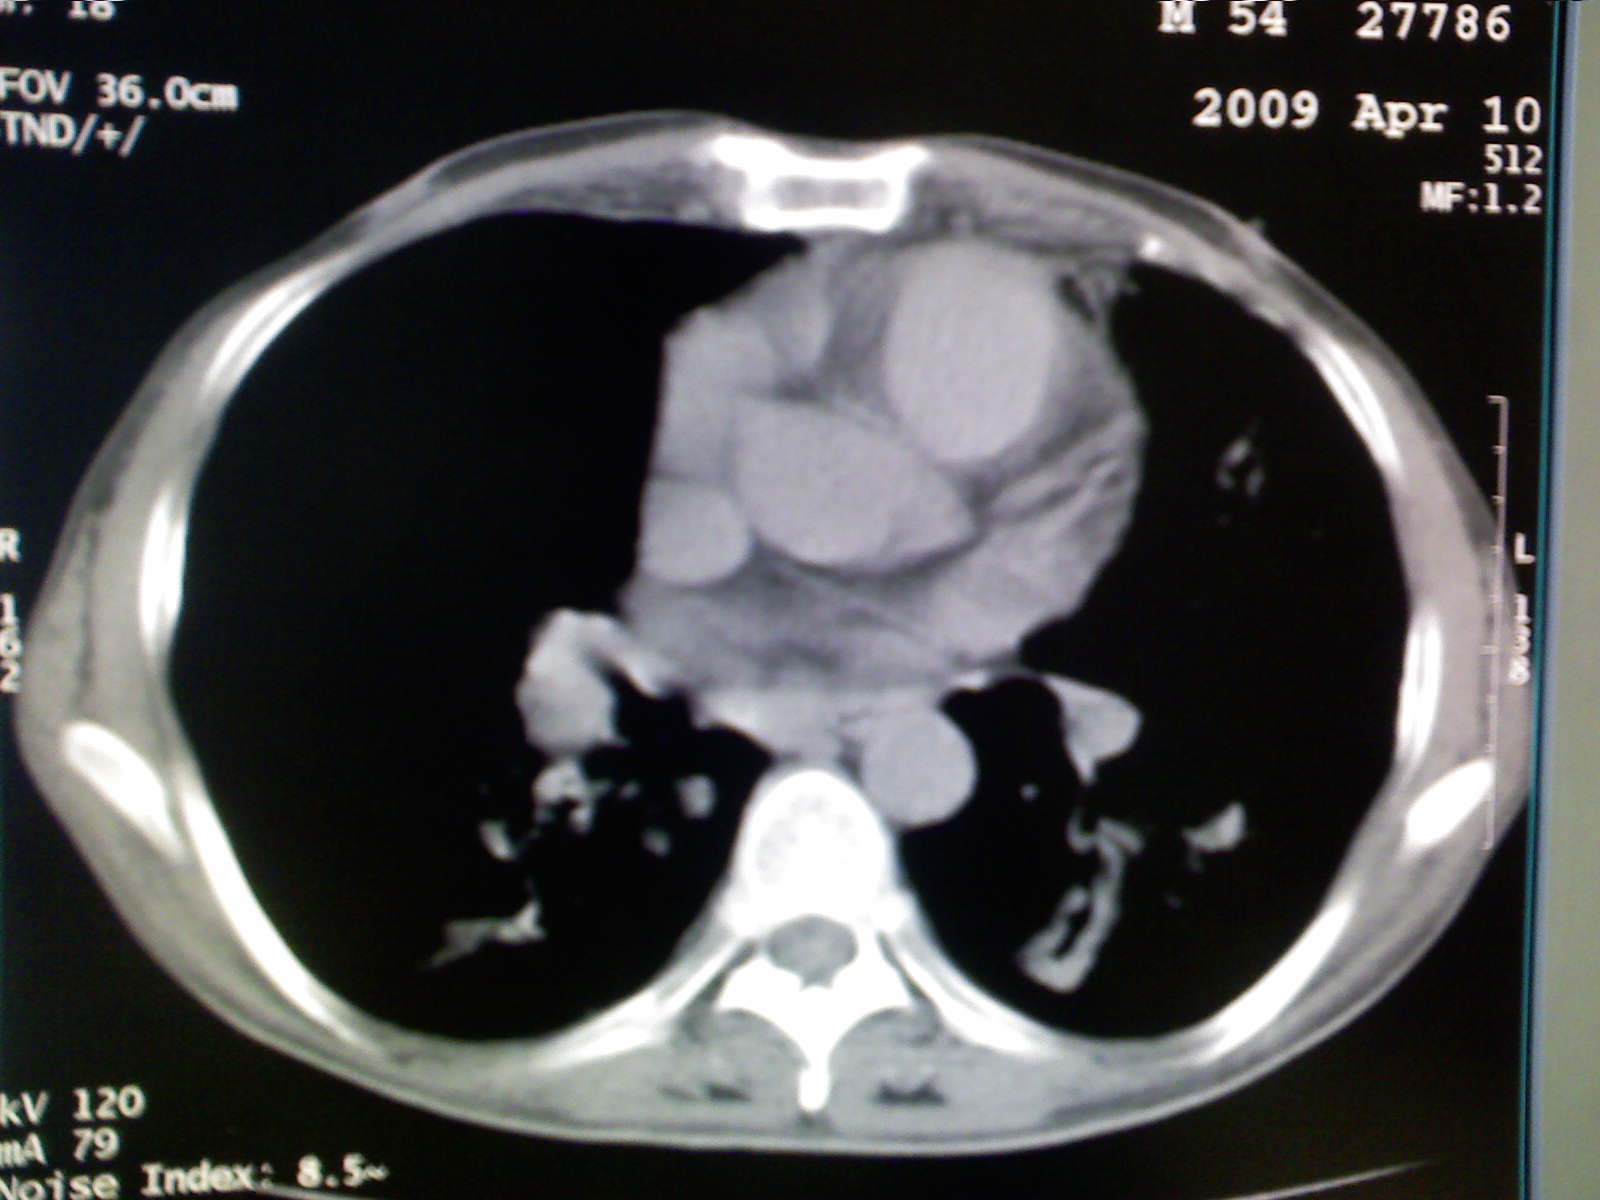

以下是引用卜一在2009-4-11 15:50:00的发言:[br]双肺继发性肺结核伴空洞形成,不排除合并霉菌感染!(病灶呈多形态 多特征 散在分布)。另:合并支气管扩张征伴感染!

以下是引用主力军在2009-4-11 15:55:00的发言:[br]两肺继发性肺结核可能性大。

以下是引用康鹏在2009-4-11 16:30:00的发言:[br]双肺继发性肺结核伴空洞形成合并感染[br]支气管扩张合并感染